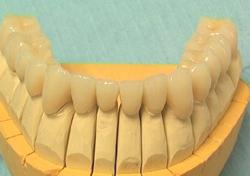

Couronnes céramo-céramiques. Réalisation prothétique Claude VALTIN (Paris).